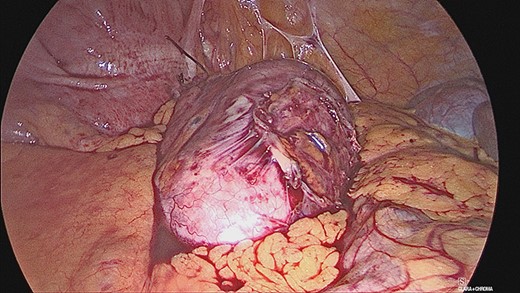

The appendiceal mucocele was visualised during the laparoscopic procedure. The adhesions surrounding the apex of the mucocele were released. There appeared to be volvulus of the appendix (Fig. 3). The main body of the appendix was normal with no evidence of malignancy seen during the surgery. On this basis, a right hemicolectomy was not performed. The appendix was amputated at the base and removed with the base tied (Fig. 4).